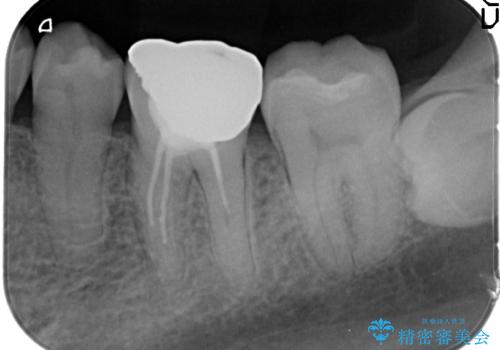

矯正治療後、右下のインレーブリッジおよび左下の銀歯のやりかえを行なっています。

右上の八重歯は、右上の奥歯を矯正用ミニスクリューを用いて遠心移動を行い解消しました。